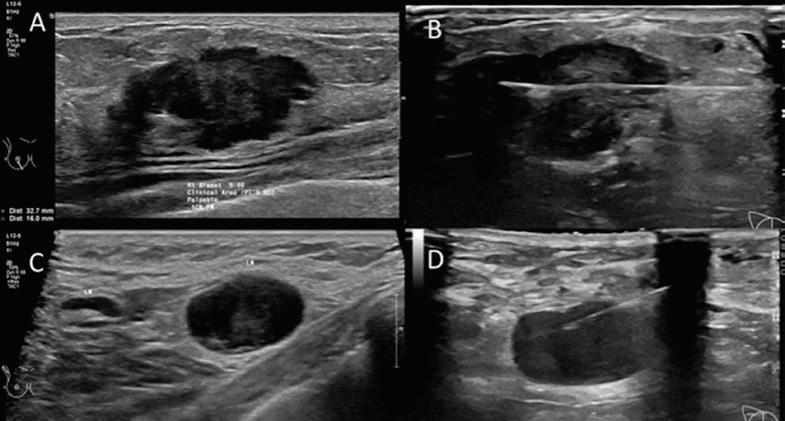

43 TKR – better outcomes Dr Gavin Clark 53 Colorectal cancer & radiation therapy Dr Eve Tiong 54 ACL Rehab – is it all in your head? Dr Casey Whife 39 MCA’s ripple effect Bruce Langoulant 61 Lasers & vascular lesions Dr Ian Skinner 37 Spinal cord treatment on the brink Emeritus Professor Byron Kakulas 59 Physical activity after COVID-19 Olivia Reynolds 56 Sickle Cell Disease Natalie Gamble-Williams & Dr Tina Carter 44 Foot surgery & total ankle replacement Dr Simon Zilko 47 Breast imaging Dr Vanessa AtienzaHipolito 49 First-time shoulder dislocations Dr David Graham Guest Columns This magazine has been printed using solar electricity, and the paper from plantation-based timber has been manufactured and printed with ISO 14001 accreditation, the highest environmental standard. MAJOR PARTNERS 36 Early language issues Dr Sam Calder & Dr Lizz Hill